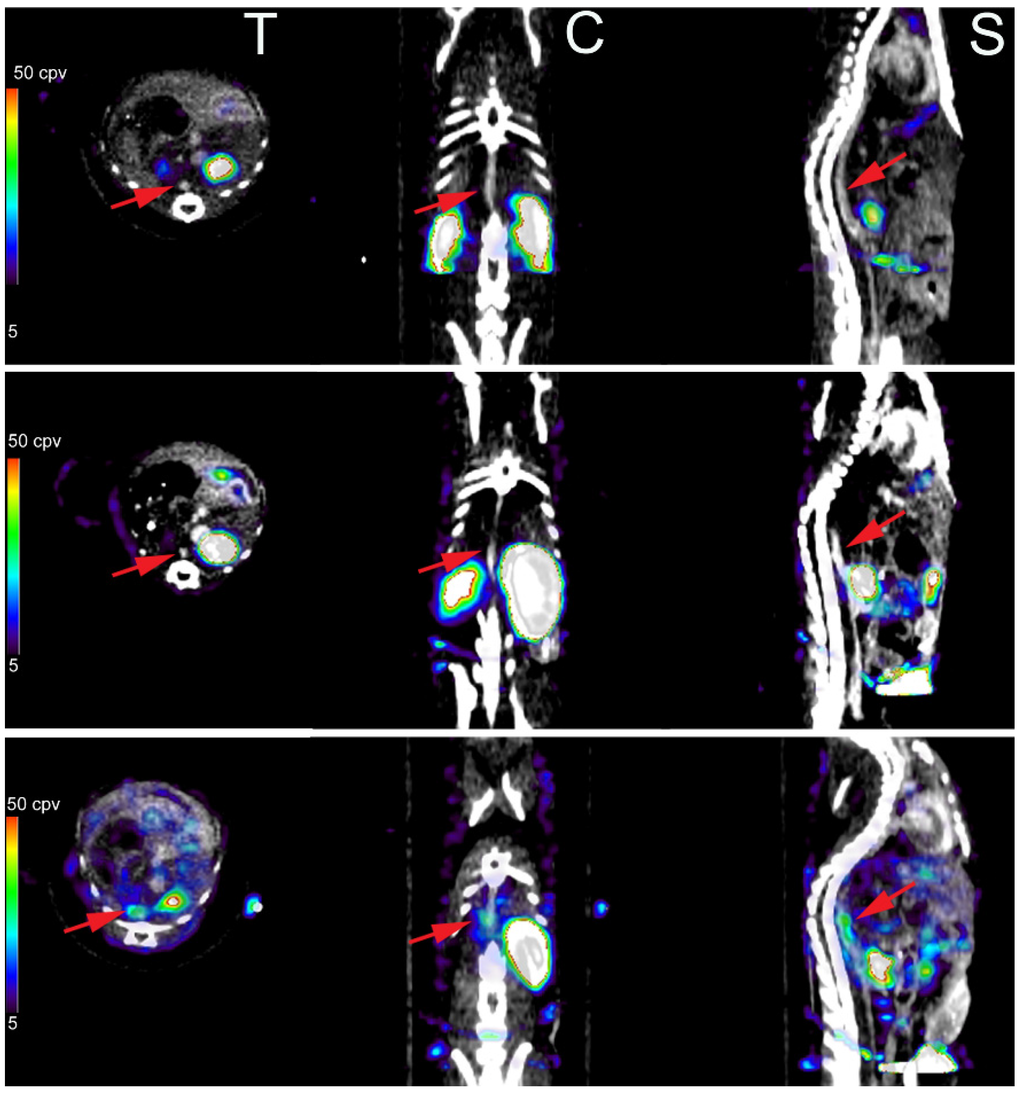

- Golestani, R.; Razavian, M.; Nie, L.; Zhang, J.; Jung, J.J.; Ye, Y.; de Roo, M.; Hilgerink, K.; Liu, C.; Robinson, S.P.; et al. Imaging vessel wall biology to predict outcome in abdominal aortic aneurysm. Circ. Cardiovasc. Imaging 2015, 8, e002471. [Google Scholar] [CrossRef] [PubMed]

- Jung, J.J.; Razavian, M.; Challa, A.A.; Nie, L.; Golestani, R.; Zhang, J.; Ye, Y.; Russell, K.S.; Robinson, S.P.; Heistad, D.D.; et al. Multimodality and molecular imaging of matrix metalloproteinase activation in calcific aortic valve disease. J. Nucl. Med. 2015, 56, 933–938. [Google Scholar] [CrossRef] [PubMed]